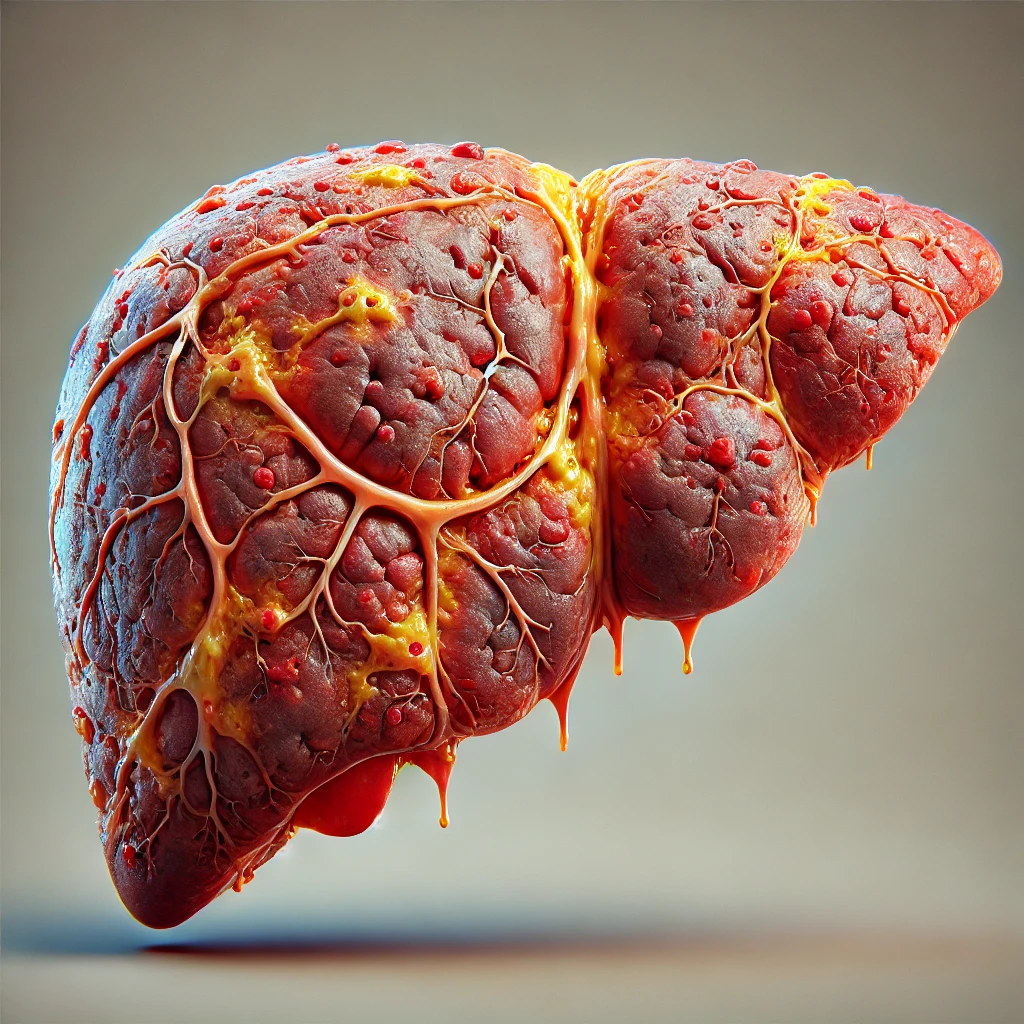

Veja a evolução da gordura no fígado não tratada.

A gordura no fígado não tratada pode evoluir de forma gradual. Inicialmente, ocorre a esteatose hepática (fígado gorduroso), onde há acúmulo de gordura nas células do fígado. Se não for tratada, pode progredir para esteato-hepatite não alcoólica (NASH), caracterizada por inflamação no fígado. Isso pode levar à fibrose hepática, com formação de cicatrizes no fígado, e, se persistir, evolui para cirrose hepática, onde o fígado perde a capacidade de funcionar corretamente, podendo resultar em insuficiência hepática ou até câncer de fígado. O tratamento precoce pode evitar essa progressão, geralmente com mudanças no estilo de vida.

Quais são as consequências da inflamação?

Dor e inchaço Abdominal

O acúmulo de gordura no fígado é comum em pessoas com obesidade, colesterol alto ou diabetes, podendo ser assintomático ou provocar sintomas como dor do lado direito do abdômen e barriga inchada.

Fadiga e Cansaço Excessivo

Nos estágios mais leves é possível observar algumas características bem comuns como fraqueza, cansaço, boca amarga, perda de apetite e dor de cabeça.

Evolução da esteatose hepática.